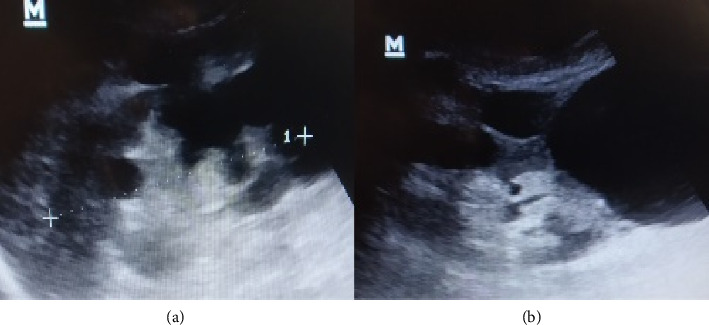

背景:常染色体显性多囊肾病(ADPKD)的特点是弥漫性肾囊肿分泌细胞因子,诱导间质炎症和纤维化。同时,急性小管间质性肾炎(ATIN)的特征是间质炎症浸润,肾活检仍然是诊断的主要方法。病例介绍:85岁男性,主诉疲劳、食欲不振、低烧一周。在过去的一个月里,患者因尿路感染(UTI)接受了环丙沙星治疗,并出现了流感症状。病史包括ADPKD 2型,基线血清肌酐(sCr)为1.2 mg/dL。实验室示急性肾损伤(AKI) (sCr = 3.98 mg/dL)。结合既往用药和感染暴露、全身性症状和AKI提示诊断为ATIN。皮质类固醇(CS)治疗后,肾功能和临床状况得到改善,sCr恢复到2.4 mg/dL。不幸的是,患者死于严重的社区获得性肺炎。结论:该病例突出了ADPKD患者的ATIN诊断困境,是ADPKD患者中第一例ATIN。由于弥漫性肾囊肿,本例ADPKD患者无法进行肾活检以进行ATIN诊断。此外,活检可能与早期ADPKD活检中出现的间质纤维化和浸润混淆。临床医生可根据新发AKI与此类ADPKD患者的临床病史和实验室检查相结合,建议进行ATIN诊断并开始治疗。CS治疗后肾功能的改善也可支持ATIN的诊断。

Background: Autosomal dominant polycystic kidney disease (ADPKD) is characterized by diffuse renal cysts that secrete cytokines, which induce interstitial inflammation and fibrosis. Meanwhile, acute tubulointerstitial nephritis (ATIN) is characterized by inflammatory infiltrates in the interstitium, where kidney biopsy remains the mainstay for diagnosis. Case Presentation: An 85-year-old male complained of fatigue, loss of appetite, and low-grade fever for a week. Within the past month, the patient received ciprofloxacin for a urinary tract infection (UTI) and described flu symptoms. The medical history consisted of ADPKD type 2 with baseline serum creatinine (sCr) at 1.2 mg/dL. Labs showed acute kidney injury (AKI) (sCr = 3.98 mg/dL). The combination of previous drug and infection exposure, systemic symptoms, and AKI suggested the diagnosis of ATIN. The kidney function and clinical status improved with corticosteroids (CS) treatment, where sCr returned to 2.4 mg/dL. Unfortunately, the patient died due to severe community-acquired pneumonia. Conclusion: This case highlighted the dilemma of ATIN diagnosis in a patient with ADPKD and presents the first case of ATIN in ADPKD patients. Kidney biopsy was unable to be performed for ATIN diagnosis in this ADPKD patient due to diffuse renal cysts. Also, the biopsy could be confused by interstitial fibrosis and infiltrates that appeared early in ADPKD biopsies. Clinicians could suggest an ATIN diagnosis and start treatment based on the combination of new-onset AKI aligned with clinical history and laboratory tests in such ADPKD patients. Also, the improvement of kidney function after CS treatment could support the ATIN diagnosis.